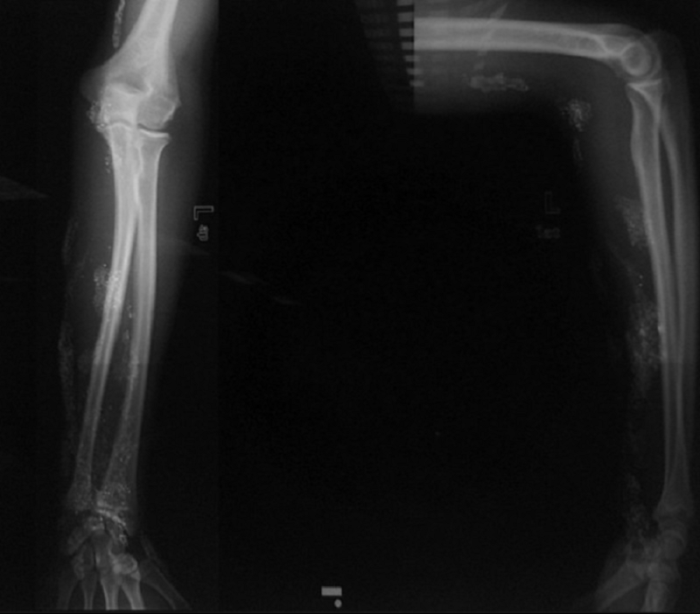

Рентгеновский снимок (переднезадний и боковой виды), показывающий множественные подкожные отложения рентгеноопаски